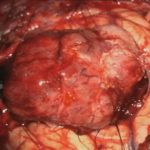

下垂体腺腫

No.’25_102  摘出 中